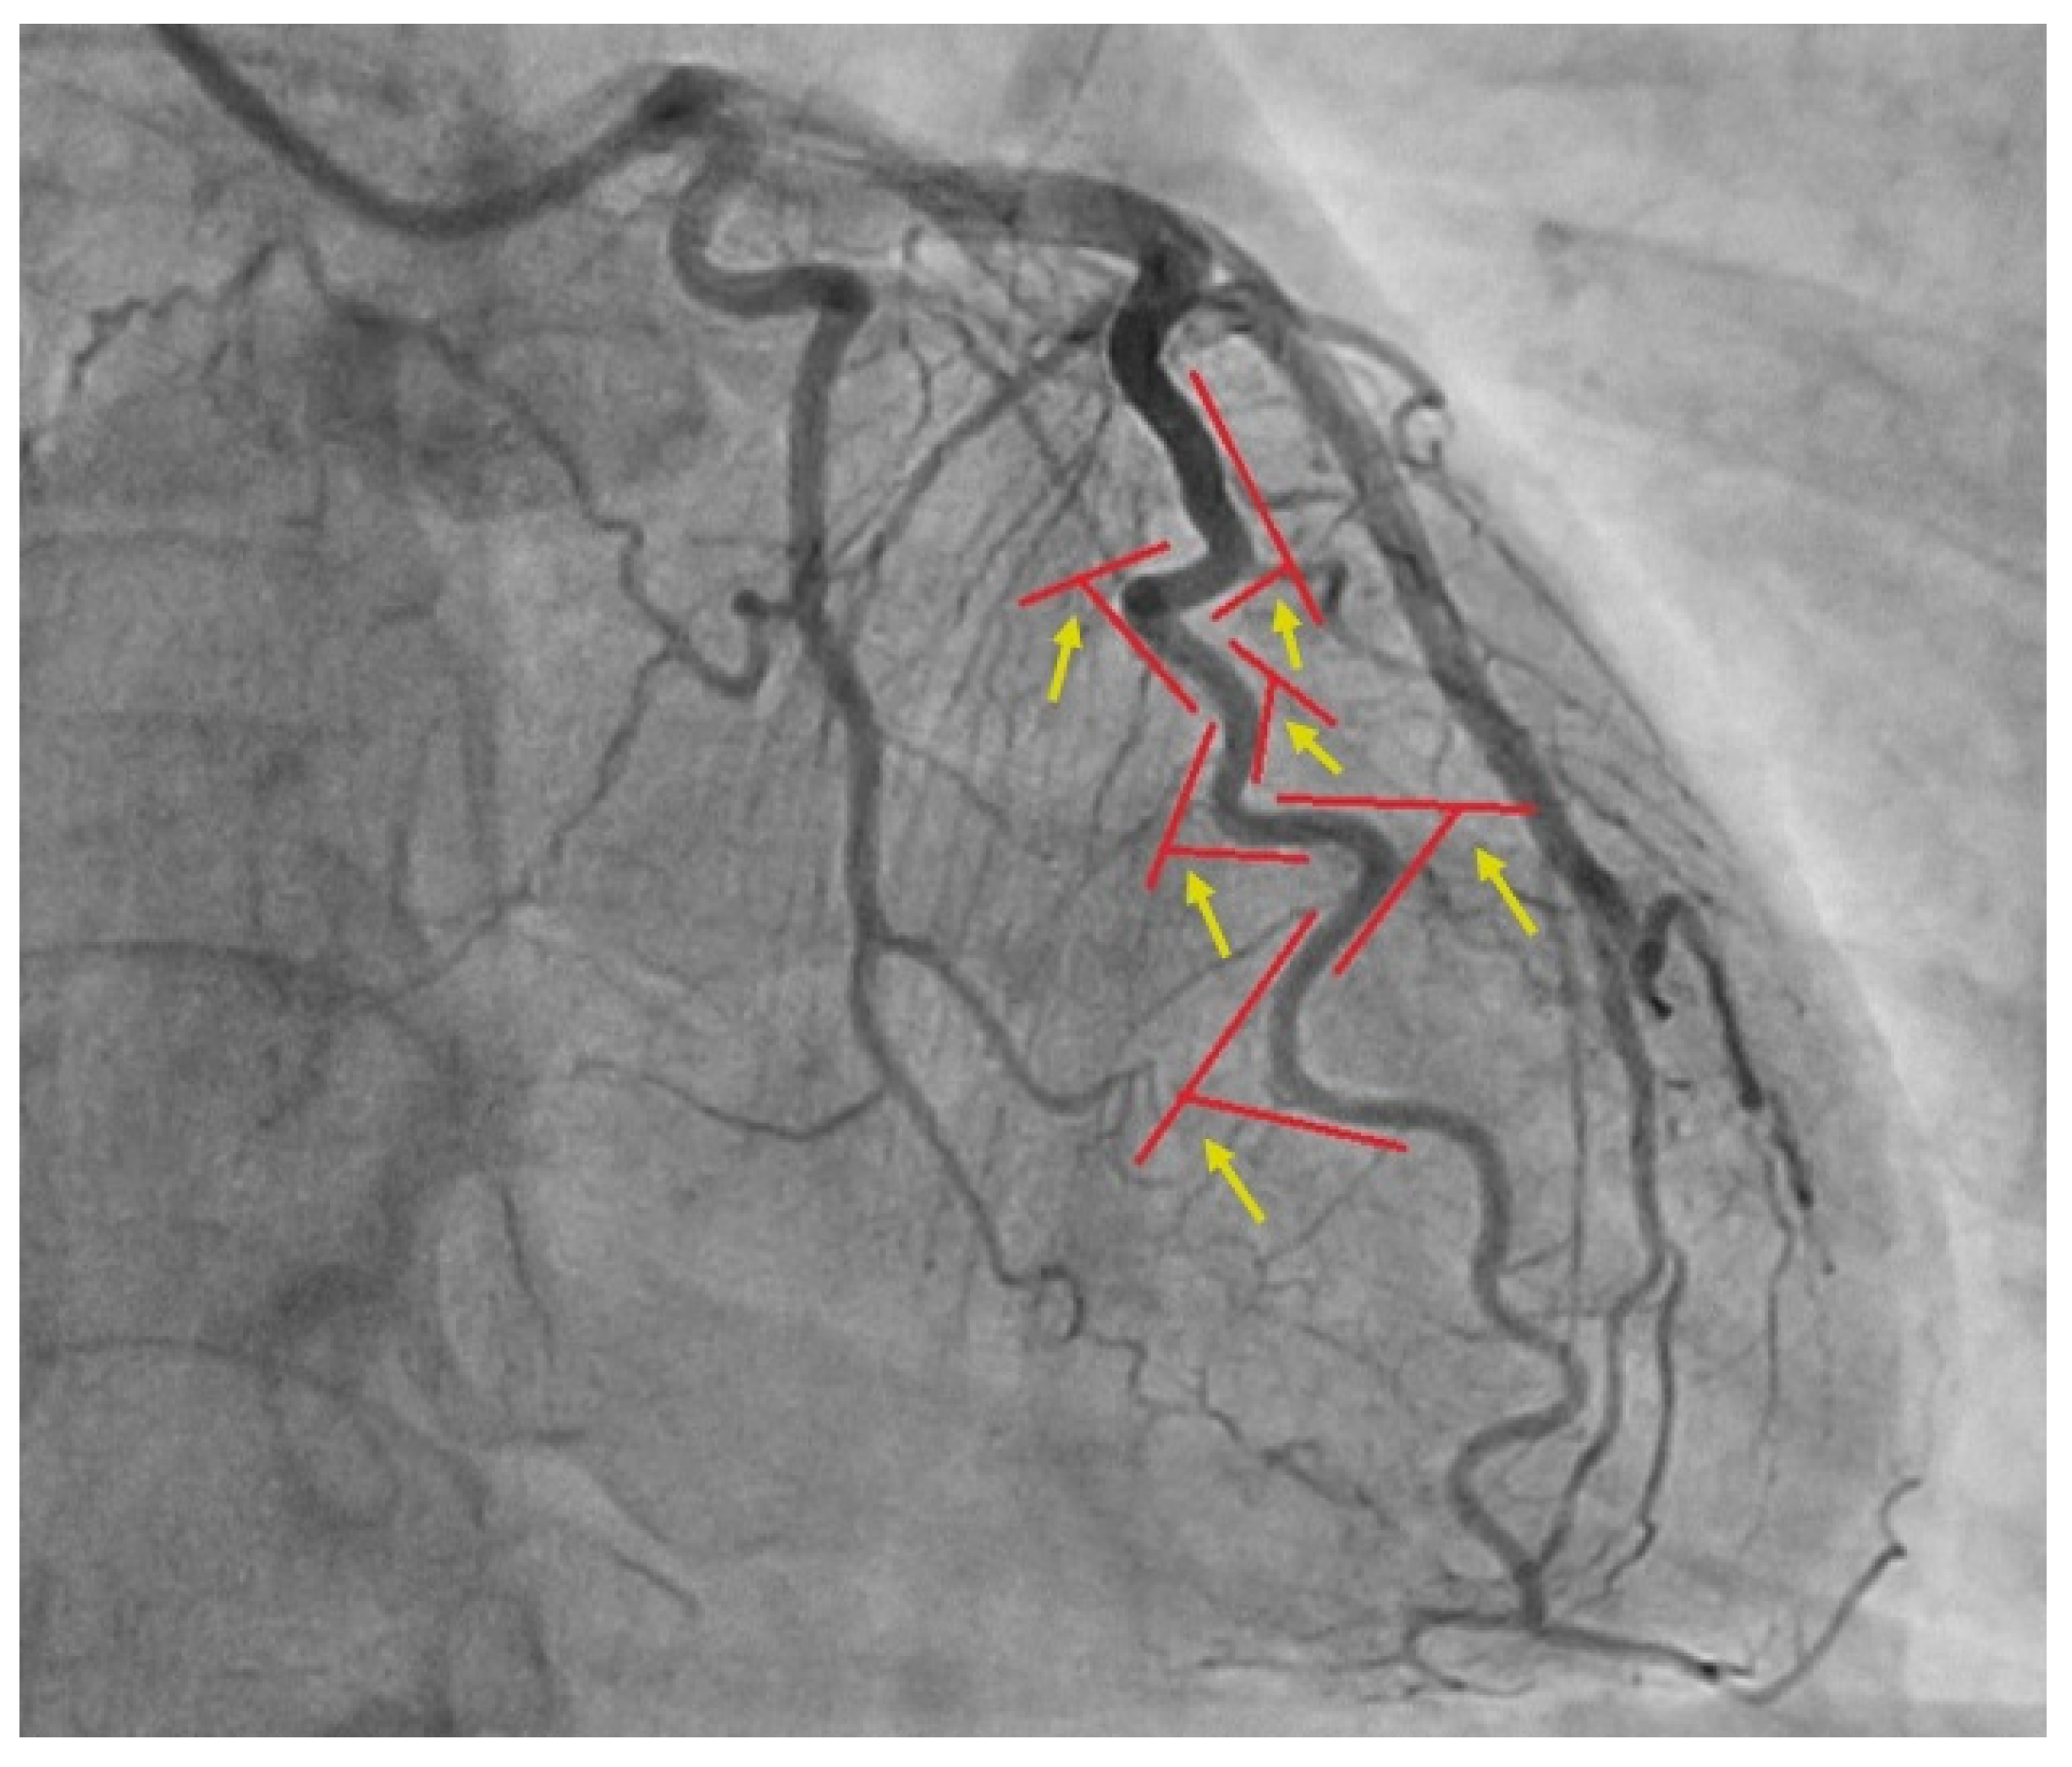

Coronary Tortuosity Index vs. Angle Measurement Method for the Quantification of the Tortuosity of Coronary Arteries in Non-Obstructive Coronary Disease

2. Materials and Methods